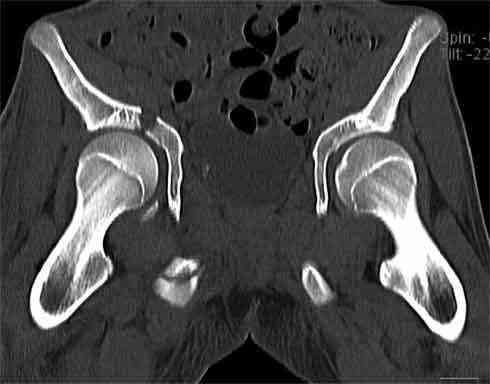

Не смог разглядеть на представленных картинках частичное повреждение левого КП, повреждение Денис1-2 справа? 3Д реконструкции в инлет и боковой проекциях убедительно не демонстрируют типа повреждения задних отделов тазового кольца(справа боковая масса скомпремирована), Наверное, у тебя есть возможность оценить тип перелома крестца по прямой проекции 3Д.

По вертлуге- смог разглядеть только изолированный перелом передней колонны.

Насколько я понял из твоего письма, обращенного к анонимному vit, ты не видишь показаний к реконструкции перелома. Я бы взялся за реконструкцию(илео-ингвинальный доступ), хоть прошел и месяц после травмы: боковая 3Д показывает смещение нагрузочной зоны впадины, что однозначно будет способствовать разрушению хряща головки и впадины( особенно у 16 летнего пациента с ожидаемым высоким уровнем активности) + изменение геометрии впадины за счет неустраненного смещения фрагментов колонны (КТ, 3Д данные).

На мой взгляд, без реконструкции этот сустав обречен (концепция вторичной конгруэтности в данных условиях работать не будет), реконструкция дает шанс на восстановление функции сустава.

В данном случае 3D и корональные срезы КТ менее информативны, чем поперечные. Согласен с левосторенним минимальным повреждением КПС, но не смог уловить перелом крестца.

По представленным материалам, мне кажется, перелом был передней колонны ацетабулум с минимальным вовлечением нагрузочной поверхности сустава, левосторенний повреждение КПС и лонных костей.

При свежем случае показана фиксация передней колонны к задней (снимки), компрессирующим винтом минимальным перкутанным методом по супраацетабулярной линии и в зависимости от состояния КПС.